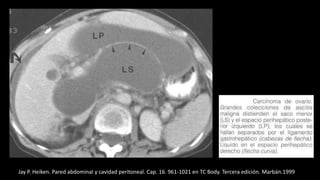

Ascitis de causa renal

Jay P. Heiken. Pared abdominal y cavidad peritoneal. Cap. 16. 961-1021 en TC Body. Tercera edición. Marbán.1999